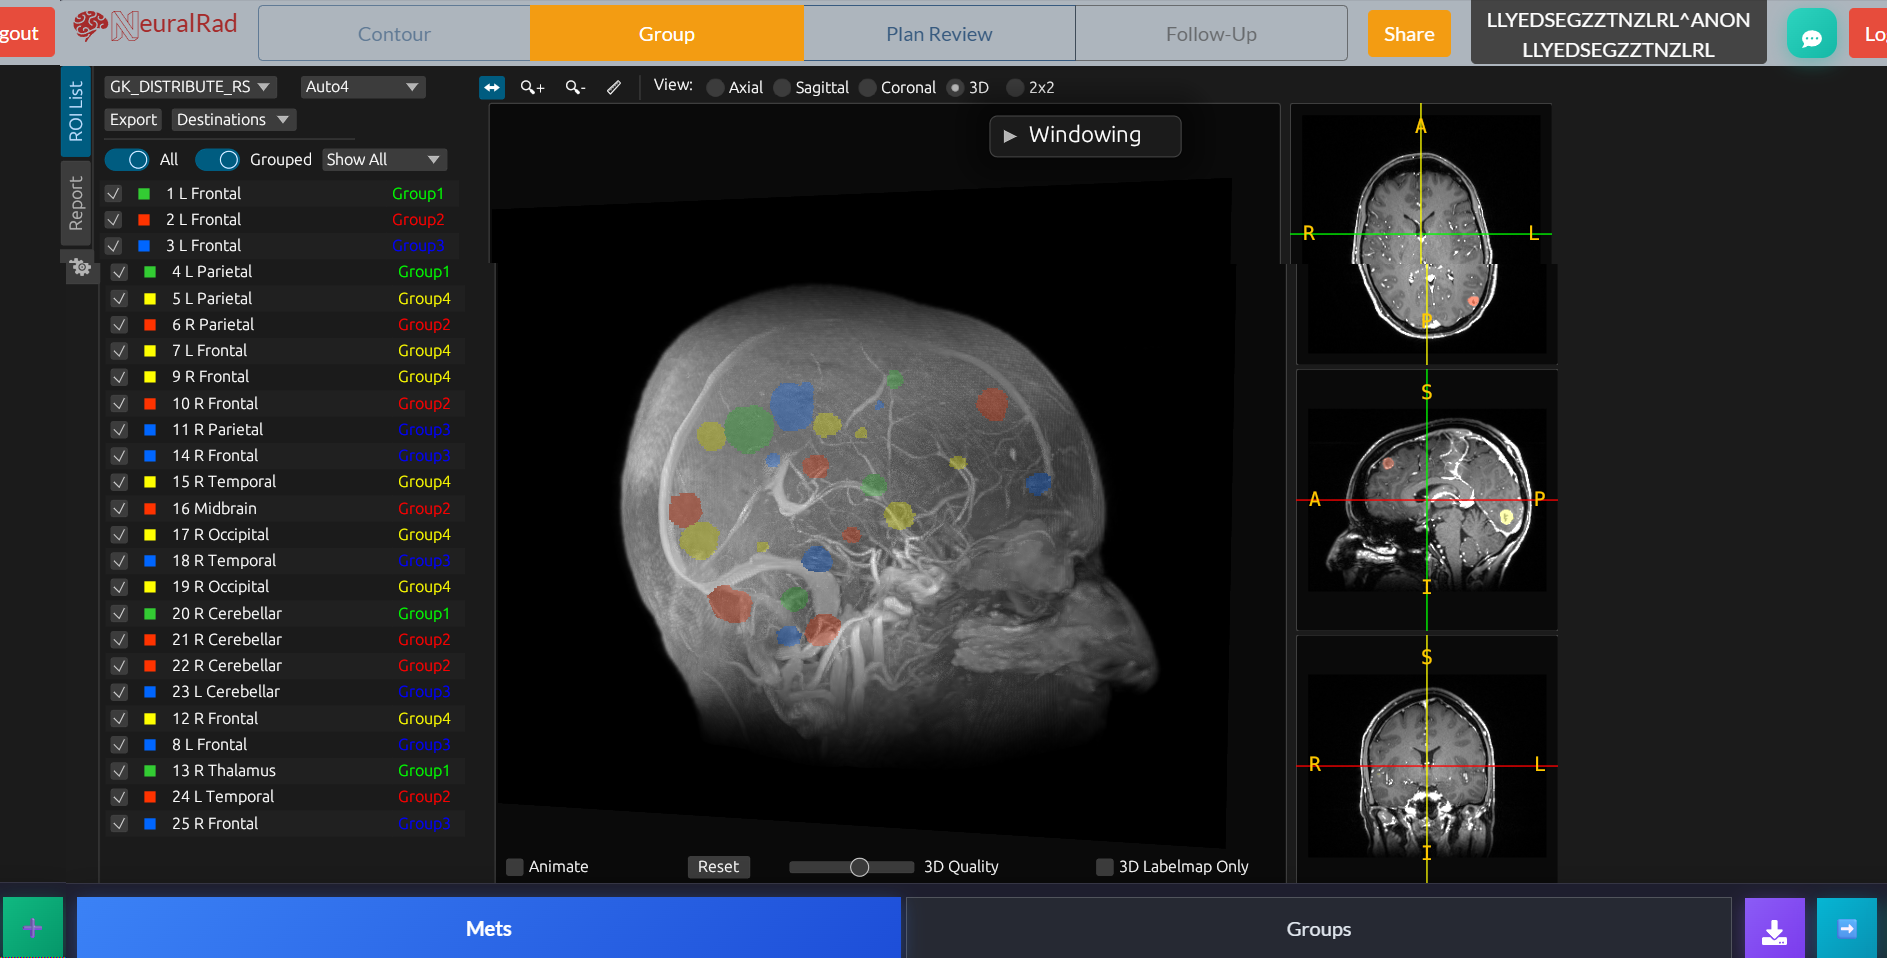

Brain

AI-Powered Stereotactic Radiosurgery Platform

Revolutionizing brain metastasis treatment with automated lesion detection, segmentation, and multi-course tracking. Built for radiation oncologists who demand precision.